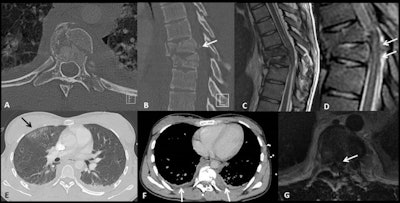

A 22-year-old female sustained a high-speed fall after a jump, during a competition. She presented with acute paraplegia. CT scan performed with polytrauma protocol (axial plane in A, sagittal plane in B with bony window) shows a burst fracture of T8 (with involvement of its left transverse process and with a posterior bone fragment displacement into the spinal canal, arrow in B), T9, and T10 vertebrae. A subsequent MRI obtained on the same day shows spinal cord compression (note the retropulsed bone fragment in contact with the spinal cord on axial T2-weighted image in G), spinal cord contusion that appears hyperintense on sagittal T2-weighted (C), and STIR sequence (D) and a posterior epidural hematoma (arrow in D). Thoracic CT scan shows a lung contusion (arrow in E) and bilateral pleural effusion (F).

A 22-year-old female sustained a high-speed fall after a jump, during a competition. She presented with acute paraplegia. CT scan performed with polytrauma protocol (axial plane in A, sagittal plane in B with bony window) shows a burst fracture of T8 (with involvement of its left transverse process and with a posterior bone fragment displacement into the spinal canal, arrow in B), T9, and T10 vertebrae. A subsequent MRI obtained on the same day shows spinal cord compression (note the retropulsed bone fragment in contact with the spinal cord on axial T2-weighted image in G), spinal cord contusion that appears hyperintense on sagittal T2-weighted (C), and STIR sequence (D) and a posterior epidural hematoma (arrow in D). Thoracic CT scan shows a lung contusion (arrow in E) and bilateral pleural effusion (F).Angiography with embolization has a pivotal role in the treatment of vascular and parenchymal injuries, they pointed out. "Radiography is the first-line tool in the evaluation of a bony injury of the upper and lower extremities. Ultrasound still has an important role in minor blunt abdominal trauma, particularly in the pediatric population due to the absence of ionizing radiation."